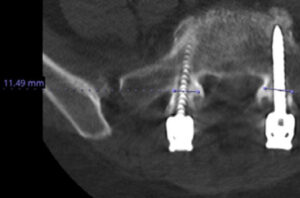

Dr. Paul Krafft places iFuse Bedrock Granite® in the S1 pedicle and S2AI trajectories following L5-S1 hardware loosening and pseudarthrosis.